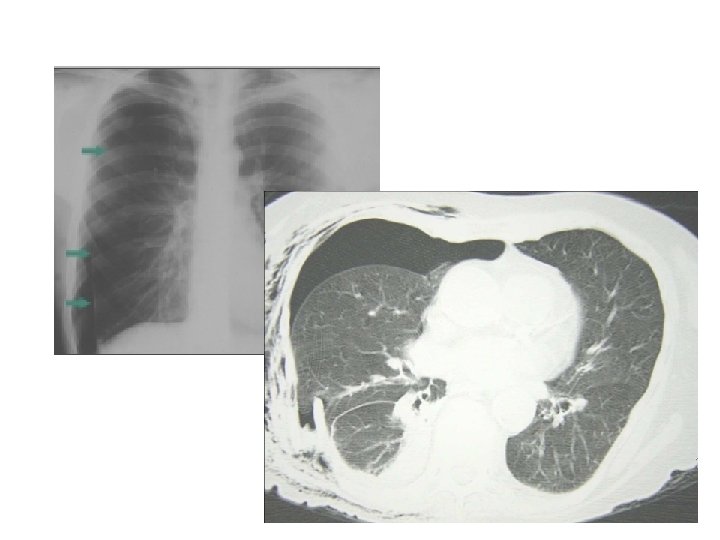

Pneumothorax suffoquant